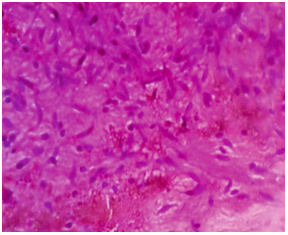

Figure 8: FNAC fibrillary matrix and mild mixed inflammatory infiltrate and RBCs

Fine needle aspiration cytology (FNAC) from the site of the lesion showed moderate cellularity with benign cells in clusters. Cells were spindle to oval with scant to moderate amount of cytoplasm. Background showed fibrillary matrix and mild mixed inflammatory infiltrate and RBCs (Figure 8).

Features were suggestive of benign spindle cell tumor probably of neurogenic origin-Schwannoma was considered.